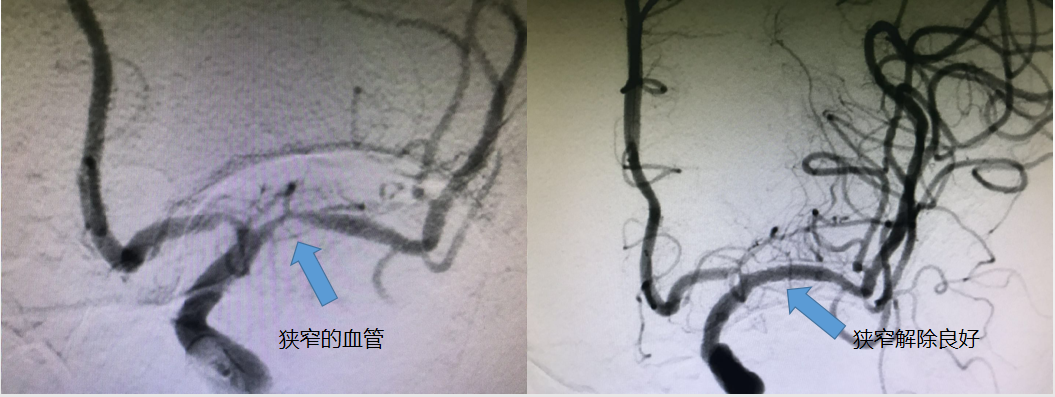

案例2

术前术后对比图

患者徐女士,女,65岁,因反复头晕1月后入院,患者1月前无明显诱因出现头晕不适,反复多家医院就诊,效果欠佳,听说了区人民医院的脑卒中中心,专门找到王司清主任来就诊,王主任认真询问病史,仔细查体,颅脑MRI检查示:左侧半卵圆中心急性期脑梗死,为低灌注分水岭性脑梗死,进一步评估脑血管,头颈部CTA示:左侧大脑中动脉起始部重度狭窄,有支架置入血管成形术的治疗指征。遂于7月17日在全麻下行左侧大脑中动脉支架置入血管成形术。再次造影显示血管狭窄解除良好,术毕,安返病房,积极监护治疗2天后,未诉不适,现已康复出院。